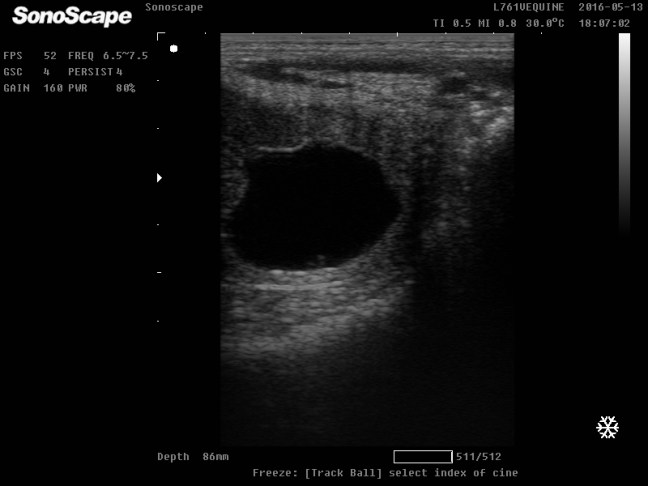

Ocena momentu owulacji u klaczy - Kontrola źrebności klaczy badaniem USG- dzięki zastosowaniu ultrasonografii ciążę możemy potwierdzić już w 9 dniu po owulacji, jednak największą wartość diagnostyczną mają badania przeprowadzone w 21 dniu po owulacji.

Ciąża 21 dni od owulacji - Leczenie niepłodności– płukanie macicy, leczenie zakażeń śródmacicznych.